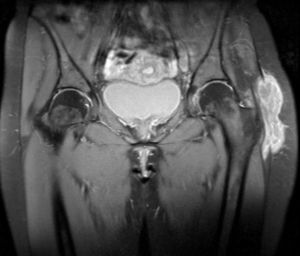

En el momento de la consulta refería dolor de características inflamatorias en la región peritrocantérea izquierda, irradiado hacia el glúteo, la región inguinal y la rodilla, con dificultad para la deambulación, sin historia de traumatismo, fiebre ni síntomas constitucionales. A la exploración se observó un aumento de partes blandas a dicho nivel, en ausencia de otros signos inflamatorios, junto a una marcada limitación a la movilización activa y pasiva de la articulación coxofemoral en todos sus planos. No presentaba afectación de otras articulaciones ni clínica respiratoria. En el control analítico se objetivó un recuento linfocitario de 13.000/μl y velocidad de sedimentación globular de 35mm en la primera hora. El Mantoux fue positivo. La radiografía de tórax fue normal. En la imagen radiológica (fig. 1) de la cadera se observó aumento de partes blandas en la región del trocánter izquierdo, sin signos de afectación ósea. Se realizaron una ecografía y una resonancia magnética de dicha cadera en las que se objetivó la presencia de bursitis trocantérea. Se realizó una punción-aspiración guiada por ecografía de la zona abscesificada y se obtuvo de material tipo caseum. El cultivo del material obtenido demostró la presencia de Mycobacterium tuberculosis (M. tuberculosis).

La TBC musculoesquéletica es más frecuente en pacientes inmunodeprimidos. El caso que presentamos se trata de una mujer inmunocompetente, que es diagnosticada de una bursitis tuberculosa años después de completar tratamiento profiláctico. Las manifestaciones musculoesqueléticas por M. tuberculosis se suelen presentar de forma insidiosa3, en ausencia de fiebre y síntomas generales. La bursitis tuberculosa puede ser un signo de reactivación de la enfermedad. El diagnóstico se suele realizar en fases avanzadas por la presencia de abscesos fríos o fístulas4. Las imágenes de tomografía computarizada o resonancia magnética ayudan a delimitar su extensión y la existencia de afectación ósea. En la literatura se han descrito casos de reactivación de TBC incluso décadas después de la terapia tuberculostática5,6. El tratamiento de las manifestaciones musculoesqueléticas en estos casos es controvertido7,8. La recurrencia alta descrita en algunas series en pacientes tratados sólo con tuberculostáticos, hace que el abordaje quirúrgico deba considerarse en todos los pacientes. En aquellos casos con afectación trocantérea extensa, se recomienda retrasar la cirugía varias semanas mientras que el paciente recibe tratamiento tuberculostático para reducir el riesgo de diseminación de la micobacteria durante la intervención quirúrgica4, tal y como se realizó en el caso que se presenta.